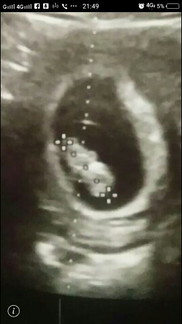

9สัปดา2วันลูกแขงเเรงโตตามเกณค่ะแต่หมอตรวจเลือดพบว่าหนุกับแฟนเปนพาหะธารัสซีเมียทั้ง2คนเด็กมีโอกาสซีด25%โอกาส1ใน4หนุจะทำยังงัยดีคะ